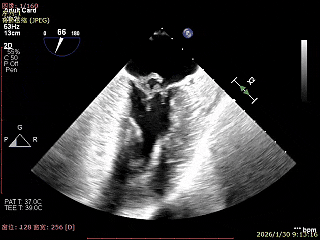

夹子释放后,反流基本消失

LVOT切面可见主瓣二尖瓣术后反流基本消失

植入两枚夹子后二尖瓣平均跨瓣压差2mmHg